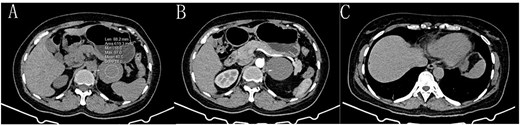

During surgery, a lump was identified behind the tail of the pancreatic body, with no apparent adhesion or invasion of the surrounding area. The pancreatic tail was completely freed and suspended along with the splenic artery and vein, revealing that the mass originated from the lesser curvature of the stomach (Fig. 2). After fully dissociating the mass, the gastric tissue was separated from it along the lesser curvature, and the mass was completely removed from the surface of the left renal vein. The mass, visible to the naked eye, measured approximately 5 × 6 cm (Fig. 3), and yellow viscous content was observed upon incision. Postoperative pathological examination revealed a retroperitoneal mass. The fibrous cyst wall tissue was lined with ciliated columnar epithelium, with numerous foam cells and lymphocyte infiltration, suggesting a diagnosis of bronchogenic cyst (Fig. 3). The postoperative diagnosis included gastric bronchogenic cyst, gallbladder stones with chronic cholecystitis, and coronary atherosclerotic heart disease. The patient received postoperative symptomatic treatment, including antiinfection therapy and fluid replacement. A follow-up abdominal CT scan six days after surgery showed no obvious residual cysts (Fig. 1C), and the patient was discharged.

Cyst (*), pancreas (☆), lesser curvature of the stomach (△). A: The cyst originates from the lesser curvature of the stomach, located posterior to the pancreas. B: The cyst is adjacent to the lesser curvature of the stomach. C: The cyst after separation from the surrounding tissue (→ indicating the broken end).